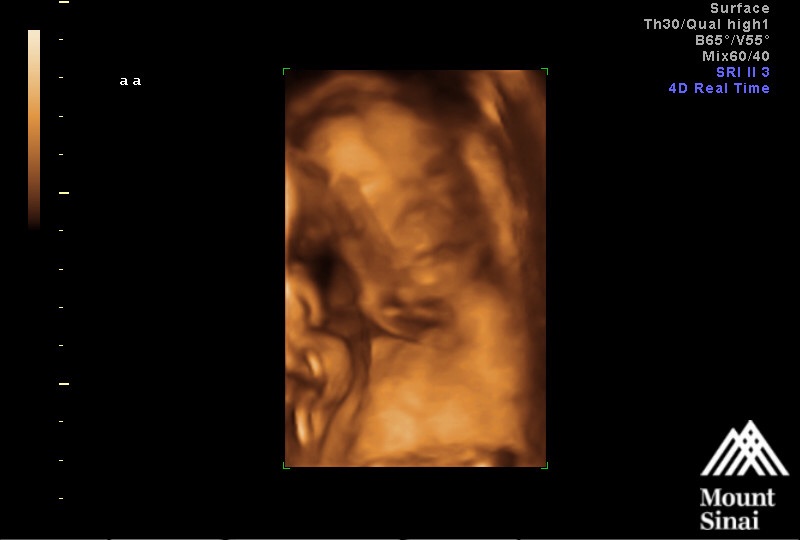

23 weeks! Please excuse my sloppiness, Im battling a nasty cold. That was the best I could do! U/S is from our Echocardiogram on Monday. Baby girl's heart looks perfect!